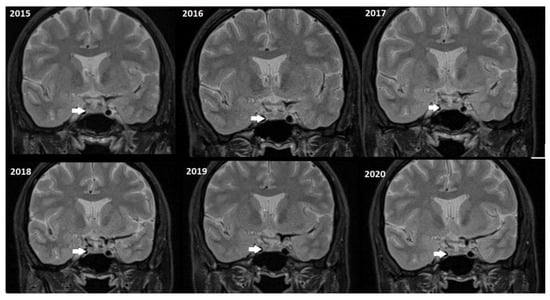

Although, the main cohort contained patients referred between 2020 and 2024, Figure 2, Figure 3 and Figure 4 shows a representative case with historical scans (2015–2020), retrieved from PACS, to demonstrate temporal stability. No evidence of recurrence of tumors in any of the nine who underwent resection of macroadenomas during this period was seen.

Figure 4.

Representative T2W coronal images (2015–2020) of a stable microadenoma (arrows) of a 33 Y/O woman. In the 5 years of follow-up, no size change can be seen.

Moreover, repeated exposure to gadolinium is associated with the deposition in basal ganglia and the dentate nuclei of the cerebellum. This deposition results in an increased signal intensity seen in T1-weighted imaging that has raised concerns concerning potential long-term neurological effects. These safety concerns are thus especially important in the case of patients with microadenomas who may require repeated MRI surveillance [38,39]. Given the fact that patients with microadenoma may be exposed more frequently to MRI with contrast, our study investigated conventional MRI and dynamic imaging for diagnosis and follow-up in patients with pituitary microadenomas undergoing MRI at our institution. We also evaluated the change in size of microadenomas in follow-up MRI studies and the necessity of injecting contrast media in monitoring this set of patients (Figure 2, Figure 3 and Figure 4).